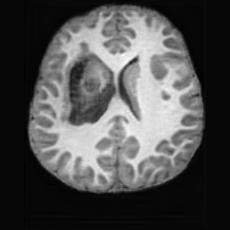

Healthy w/Lesion MaskPathologicalDifferencew/o LCGw/ LCG(a)Refer to captionRefer to captionRefer to captionRefer to captionRefer to captionRefer to captionHealthy w/Lesion MaskPathologicalDifferencew/o LCGw/ LCG(b)Refer to captionRefer to captionRefer to captionRefer to captionRefer to captionRefer to caption

Figure 7: Ablation study of Lesion Consistency Guidance (LCG). Without LCG, the generated pathological regions are indistinct and show weak pathological expression in both examples.

Lesion Consistency Guidance. Fig. 7 illustrates the impact of Lesion Consistency Guidance (LCG) for healthy-to-pathology editing. Without LCG, the generated lesion regions appear blurry around lesion boundaries, and the pathological patterns are less distinct, resulting in ambiguous lesion localization and weak pathological expression. Incorporating LCG produces lesions with more precise localization and well-defined shapes that better align with the given lesion masks, as well as textures and contrasts that exhibit stronger pathological characteristics. These results demonstrate that LCG effectively enforces lesion-aware conditioning, enhancing both spatial and semantic consistency of the generated pathological regions.